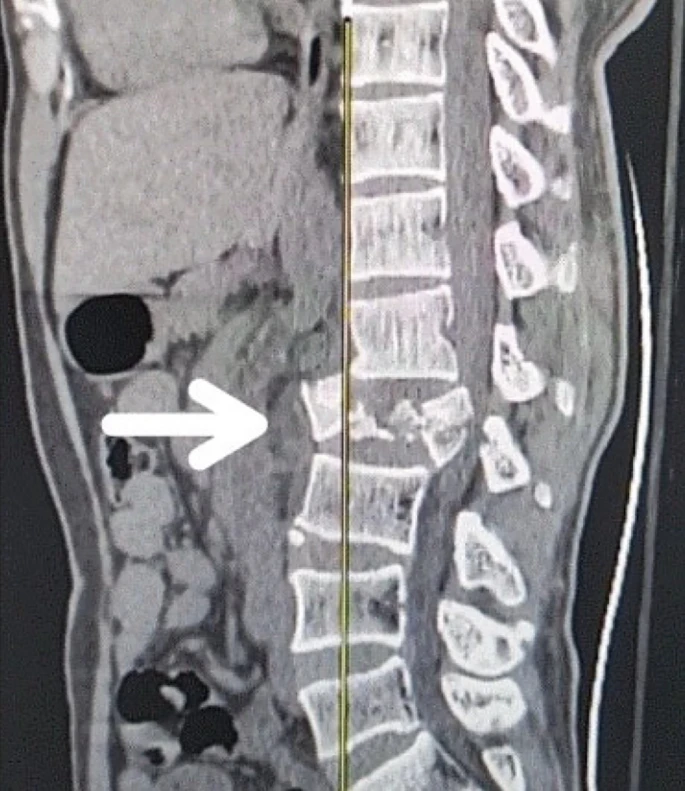

創(chuàng)傷性脊髓損傷是由于脊柱受到突然的強(qiáng)力撞擊,導(dǎo)致椎骨骨折、脫臼、擠壓或壓縮(圖1)。主要原因包括機(jī)動(dòng)車(chē)事故,其中汽車(chē)和摩托車(chē)碰撞占每年新增脊髓損傷病例的近一半。跌倒,尤其是65歲及以上人群的跌倒,是造成脊髓損傷的重要原因,約占60%。體育活動(dòng),例如沖擊性運(yùn)動(dòng)和淺水潛水,約占此類(lèi)損傷的10%。

圖1:X射線(xiàn)圖像顯示脊髓損傷,椎骨骨折和移位,如白色箭頭所示

慢性期開(kāi)始于損傷后約3-6個(gè)月,并持續(xù)患者的余生,典型特征是囊腫形成和嚴(yán)重的神經(jīng)膠質(zhì)瘢痕(圖2)。

圖2:X射線(xiàn)圖像顯示慢性期脊髓損傷,通常以囊腫形成為特征,如白色箭頭所示